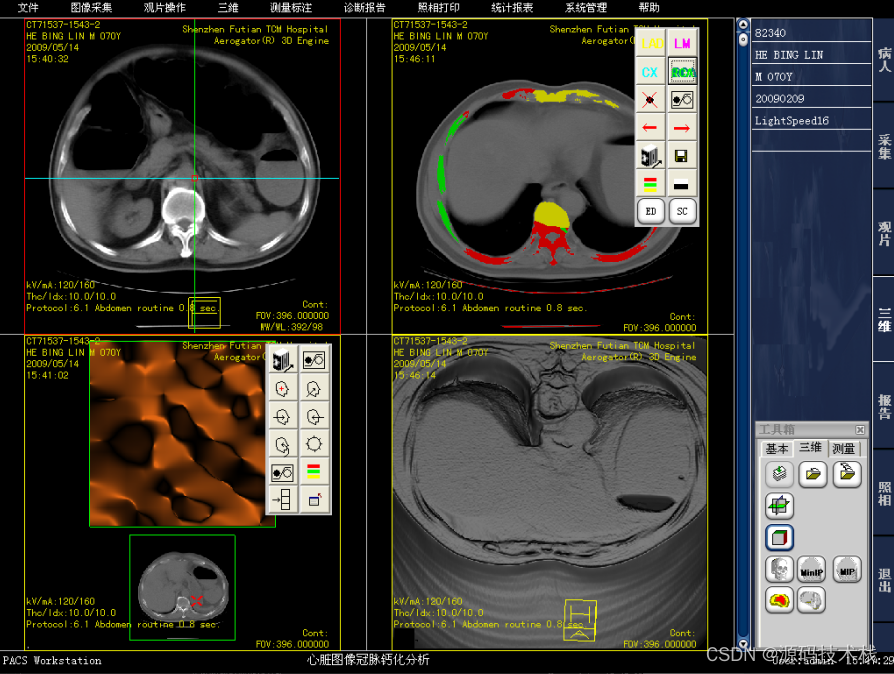

(7)图像后处理与重建

·MPR\CPR(三维多平面重建)

·VRT(三维容积重建)

·SSD(三维表面重建)

·VE(虚拟内窥镜)

·MIP(最大密度投影)、MinIP(最小密度投影)

·CalSCore(心脏图像冠脉钙化积分)